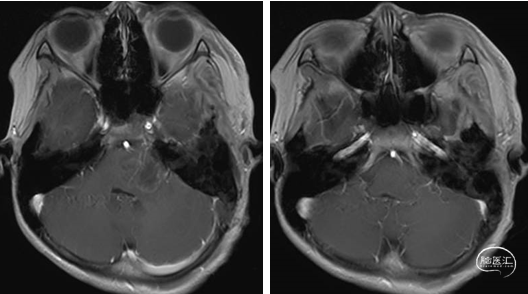

术前MRI

术后MRI